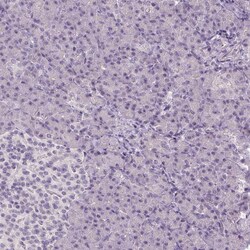

Invitrogen™ TMEM16B Polyclonal Antibody

Calcium-activated chloride channels (CaCC) are present in many cell types and mediate physiological functions such as epithelial secretion, sensory signal transduction, and smooth muscle contraction. Subunits of these CaCC's include the transmembrane proteins TMEM16A and TMEM16B. TMEM16B is predicted to have eight transmembrane domains with both the amino and carboxy termini in the cytoplasm and is expressed in several tissues including olfactory sensory neurons as well as photoreceptors in mammalian retina. Like TMEM16A, TMEM16B is thought to form at least part of CaCC's but has different biophysical characteristics such as voltage dependence and unitary conductance.

| Applications | Immunohistochemistry (Paraffin) |